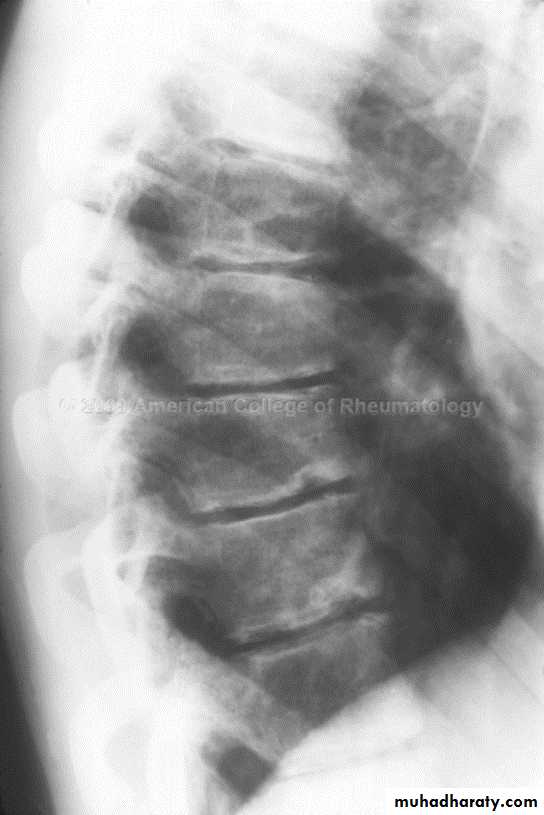

Lumbar spondylosis. There is distal narrowing and a vacuum

phenomenon is present in the degenerative discs. Marginal osteophytes arepresent. Inferiorly the facet joints show features of degeneration and, with the increase in lordosis, the spinous processes are in contact